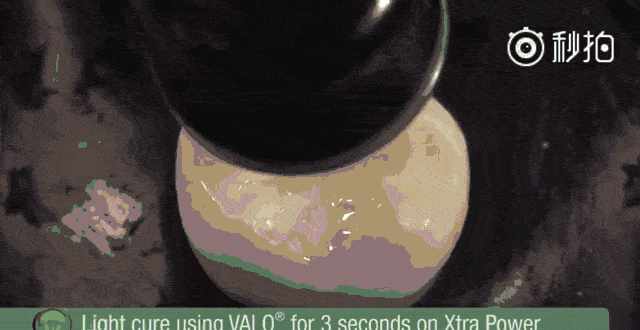

6.用特殊光照,使窝沟封闭剂变硬